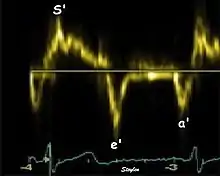

Single spectral tissue velocity curve from the mitral annulus. The curve shows velocities towards the probe (positive velocity) in systole, and away from the probe (negative velocities) in diastole. The most useful measures are the peak velocities, in systole S' and in early diastole (e') and late diastole during atrial contraction (a').

Annular velocities summarize the longitudinal contraction of the ventricle during systole, and elongation during diastole. Peak velocities are commonly used.